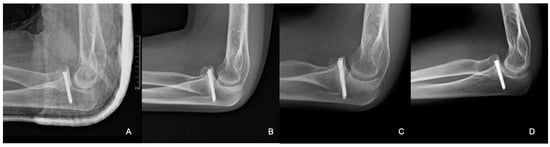

Postoperative X-rays showed the adequate position of the corticospongiosal block. After three weeks, the cast was removed and physiotherapy was initiated. After five weeks, the child complained about numbness in his ring and little fingers. At that time, his ROM was slightly limited during flexion and extension; however, his pronation–supination range was complete. Physiotherapy was continued to better the ROM of the elbow. By the third month, the joint movements were complete, with no signs of elbow instability. Control X-rays revealed signs of proper graft remodelling. By the eighth month, the fracture was healed clinically and radiologically (Figure 8).

Figure 8.

Radiographic control images from weeks 3 (A), 8 (B), 24 (C), and 40 (D).

From the X-ray imaging, it was seen that the fracture was rebuilt and the coronoid process was stabilized in a good position, with a complete ROM in the elbow joint (Figure 9).

Figure 9.